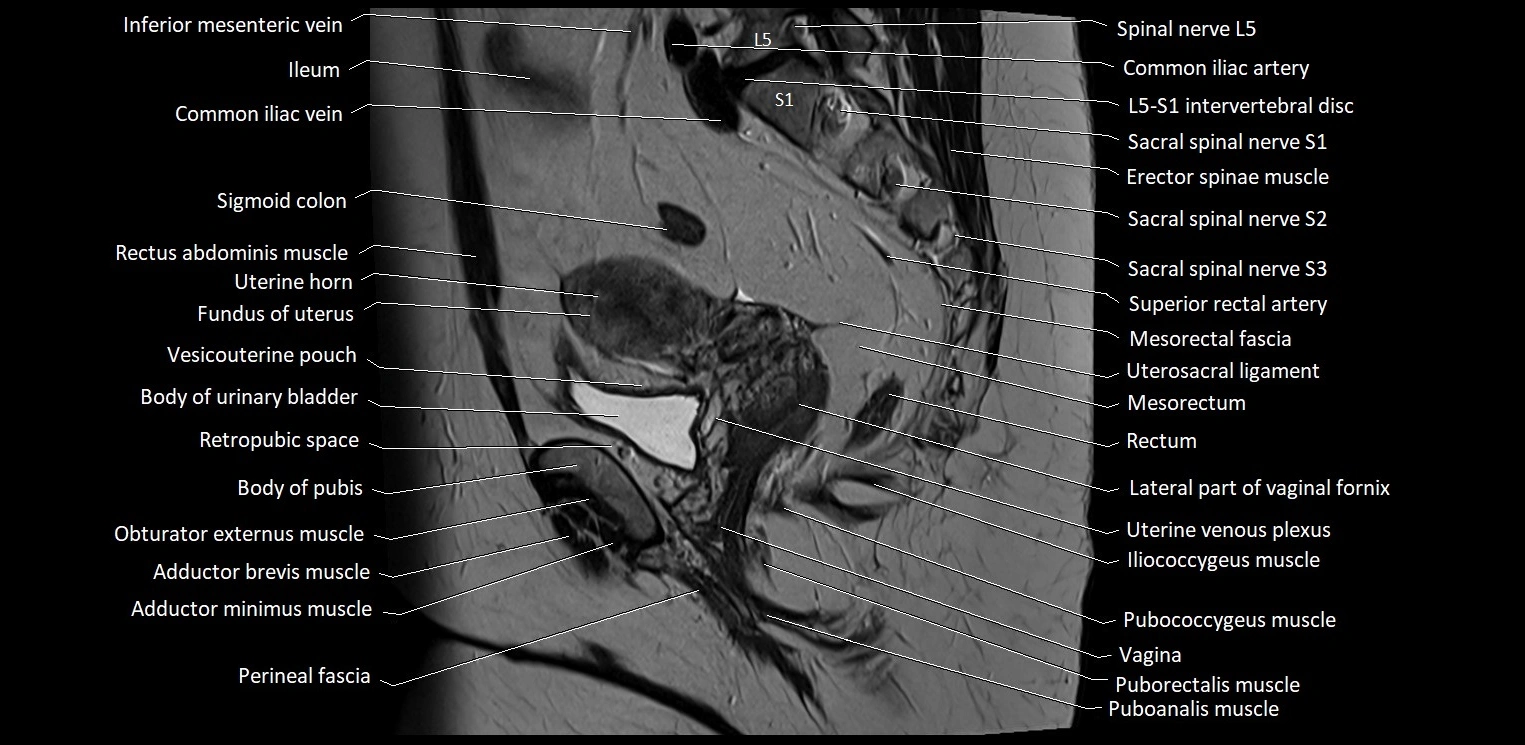

- Body of uterus

- Fundus of uterus

- Ileum

- Iliococcygeus muscle

- Pubococcygeus muscle

- Puborectalis muscle

- Rectouterine pouch (pouch of Douglas)

- Rectum

- Retropubic space

- Sigmoid colon

- Uterosacral ligament

- Vagina

- Vesicouterine pouch